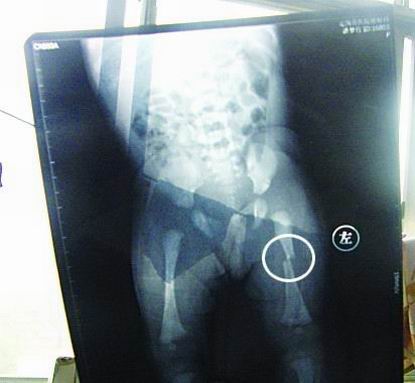

CT顯示小夢竹左下肢骨折

今年7月2日下午,定陶縣南王店鄉(xiāng)沈莊村孕婦聶元真,在定陶縣人民醫(yī)院剖腹產(chǎn)下一女嬰,取名為潘夢竹。醫(yī)院說,嬰兒出生后窒息,診斷為新生兒缺血缺氧性腦病,頭皮血腫。當晚發(fā)現(xiàn)女嬰左下肢部位異常,第二天拍片顯示為左下肢骨干骨折。7月3日,潘夢竹的頭顱CT顯示其頭頂部骨折,蛛網(wǎng)膜下腔出血,顱內(nèi)血腫。